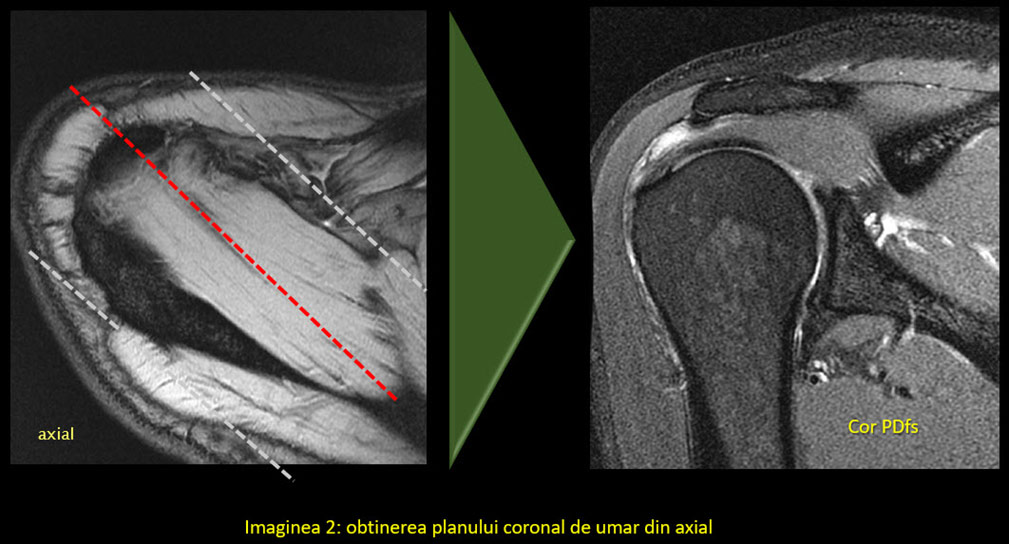

În mod normal, planurile uzual utilizate în imagistică sunt coronal, sagital și axial. În cazul umărului și majorității articulațiilor, oasele și articulațiile au o orientare specială, astfel încât se folosesc planuri modificate. Singurul plan standard este cel axial, deși poate suferi și el modificări în anumite condiții.

Utilizarea planurilor în mod corect permite evidențierea unei structuri, cum ar fi un tendon, într-o singură imagine/secțiune, fără să interfere așa numitul efect de volum parțial (adică să avem într-o imagine părți de anatomie din imaginea următoare sau precedentă). Efectul de volum parțial nu poate fi eliminat în totalitate, dar este cu atât mai mic cu cât secțiunea este mai subțire, spațiul dintre secțiuni mai mic și planul corect aliniat la anatomie.

Astfel:

• Paralel cu tendonul capului lung al bicepsului

• Perpendicular pe marginea anterioară a glenei scapulei

• Paralel/ perpendicular pe difiza humerală

• Paralele față de articulația acromio-claviculară.